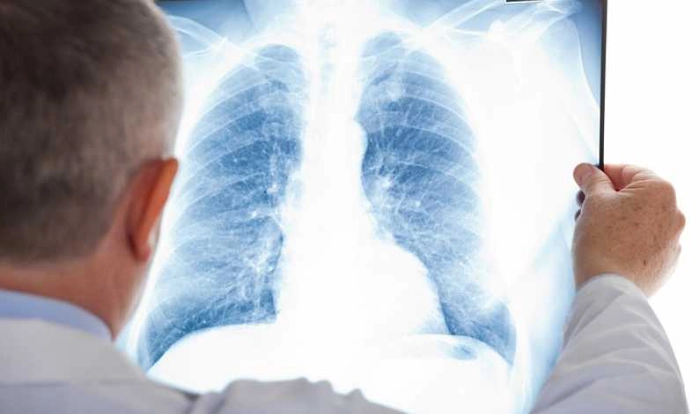

Radiografia pulmonară este recomandată de către medici din mai multe motive. Cel mai des întâlnit este verificarea stării plămânilor, pentru a exclude existența cancerului, a infecțiilor sau, chiar, colectarea aerului în spațiul dimprejurul plămânilor. Uneori, plămânii pot prezenta afecțiuni cronice, în special emfizem sau fibroză chistică, boli care pot genera numeroase complicații.

De asemenea, o radiografie la plămâni este indicată pacienților care se confruntă cu afecțiuni pulmonare, ce se află în strânsă legătură cu inima. Astfel, o radiografie de acest tip poate detecta schimbări apărute la nivelul plămânilor, care provin din afecțiuni cardiace, cum este lichidul la plămâni ca urmare al insuficienței cardiace congestive.

Se poate ca o astfel de radiografie să fie făcută pentru a afla mărimea și conturul inimii. Explicația rezidă în faptul că modificări ale dimensiunii și formei inimii pot indica insuficiența cardiacă, lichid în jurul inimii sau probleme ale valvei cardiace.

Cu ajutorul razelor X, sunt vizibile și contururile vaselor mari de lângă inimă (aorta, arterele și venele pulmonare). Acestea pot scoate în evidență anevrismele aortice, bolile cardiace congenitale sau alte probleme ale vaselor de sânge.

Radiografia la plămâni este indicată pacienților care se confruntă cu afecțiuni pulmonare, ce se află în strânsă legătură cu inima.